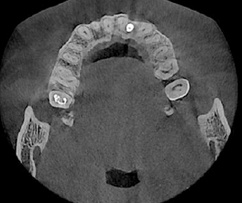

3D CT 촬영으로 치아와 치조골의 상태 및

잇몸뼈의 양과 길이 등의 상태를 정확하게

측정하여 세밀한 진단과 시술 전 발생가능한

문제점을 사전에 발견하고 대비하여

진료의 안정성을 높힙니다.

치과진료는 굉장히 세밀한 치료이기 때문에 정밀한 3D 디지털 기술을 접목하면

의료진의 판단에만 의존하던 치료를 더욱 정확하게 예측하고 진하여 오차를 줄일 수 있습니다.